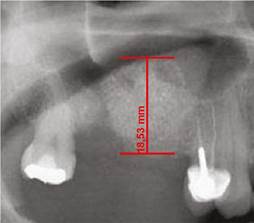

Para realizar el análisis cuantitativo de la zona de interés se digitalizaron todas las imágenes utilizando el programa AxioVision versión 3.1. La altura de hueso e injerto fue medida y ajustada de acuerdo a la magnificación, usando un factor de conversión de 25%. Las medidas iniciales se expresaron en pixeles y posteriormente fueron convertidas a milímetros, usando como referencia una regla milimetrada que fue digitalizada con cada radiografía. Se tomaron las medidas desde el punto de mayor altura de reborde alveolar en la región donde se planeaba colocar los implantes en la siguiente fase, hasta el punto donde se evidencia el cambio en radioopacidad en sentido apical dentro del seno maxilar (Figuras 1, 2 y 3).

Figura 2 Altura del reborde alveolar inmediatamente después del procedimiento quirúrgico del mismo paciente de la (Figura 1). Se aumentó la altura del reborde en 17,2 mm

La altura inicial del reborde alveolar en los pacientes del grupo 1 fue en promedio 2,9 mm (rango 0,9-4,3 mm) y en el grupo 2 fue de 3,9 mm (rango 1,4-5,4 mm). En el grupo 1 se obtuvo una ganancia en altura inicial promedio de 13,9 mm (rango 9,9-17,7 mm) y en el grupo 2 una ganancia promedio de 10,3 mm (rango 4,9-15,2mm). Seis meses después, los casos del grupo 1 presentaron una pérdida promedio de 2,9 mm (rango 0,4-3,6mm) y en el grupo 2 de solo 1,9 mm (rango 0,3-3,9mm).

Este estudio comparó la estabilidad de injertos de tibia y de hueso liofilizado (DFDB por sus iniciales en inglés decalcified freeze-dried bone) en procedimientos de elevación de seno maxilar previo a la colocación de implantes. Los resultados obtenidos muestran que los pacientes del grupo en el que se injertó hueso liofilizado presentaron diferencias significativas entre la altura obtenida inicialmente y la altura encontrada 6 meses después de haber realizado el procedimiento. Mientras que en el grupo en el que se utilizó el hueso autólogo de tibia como injerto, la altura inicial no disminuyó de manera significativa durante los 6 meses posteriores a la cirugía de elevación del piso del seno maxilar (Figuras 1 a 3).